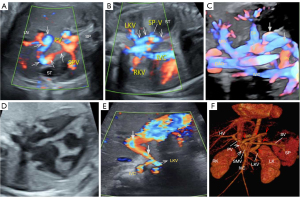

Fetuses referred to Hunan Provincial Maternal and Child Health Care Hospital for suspected malformation were scanned using the “five-plane method”, which employs high-definition flow imaging (HDFI) of the fetal abdomen across four transverse planes and one coronal plane. Each plane is labeled with different colors to clearly show the blood vessels that are easier to observe in each plane (Figure 1). The technique is demonstrated in Video 1.

v Plane 1: visualization of the intrahepatic portal venous system (IHPVS). Beginning with the fetal abdominal circumference measurement, the ultrasound probe is adjusted to visualize the umbilical vein (UV) as it enters the liver and connects to the sagittal part of the left branch of the PV, forming a “L-shaped” configuration at a right angle where the bend corresponds to the portal sinus (PS) (Figure 1A).

v Plane 2: visualization of the ductus venosus (DV). From Plane 1, the probe is adjusted in the cephalic direction of the fetus to reveal the DV, which continues from the sagittal part of the left branch of the PV, and drains into the proximal segment of the inferior vena cava (IVC) (Figures 1B).

v Plane 3: visualization of the hepatic venous system. The probe is further angled cephalically from Plane 1 to provide a clear view of the hepatic venous system. This includes the left, middle, and right hepatic veins converging into the IVC, offering a detailed assessment of hepatic venous drainage (Figure 1C).

v Plane 4: visualization of the confluence of the main portal vein (MPV) and the PS. Using the PS as a reference from Plane 1, the probe is slightly repositioned to trace the MPV and its confluence with the PS. This reveals the MPV extending into the right anterior and posterior branches, which transport hypoxic blood from the spleen and the gastrointestinal tract to the right liver lobe. Plane 4 enriches the observations initiated in Plane 1 by providing a detailed depiction of the MPV, along with its anterior and right posterior branches, enhancing the understanding of the architecture of the IHPVS (Figure 1D).

v Plane 5: coronal view of the first-order branches of the extrahepatic portal venous system (EHPVS). The probe is rotated 90 degrees from Plane 4 to capture a coronal view of the first-order branches of the EHPVS. This plane distinctly visualizes the merging of the superior mesenteric vein (SMV) and splenic vein (SV) into the MPV, along with their respective arteries (Figure 1E).